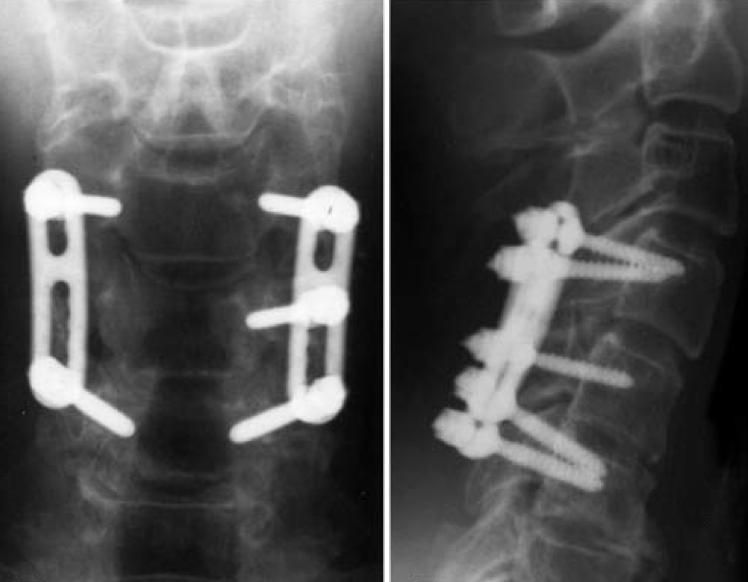

Direct Fixation of C1 Jefferson Fracture Using C1 Lateral Mass Screws What Is A Lateral Mass Fracture Separation, comminution, split, and traumatic spondylolysis. Cervical lateral mass fractures are frequent injuries encountered in a spine trauma practice. The sagittal and frontal alignments were. The lateral mass is the bony junction between the superior and inferior articular processes, separated medially from the lamina. The aim of this study was to define. Fractures of c1 occur through. Lateral mass fractures. What Is A Lateral Mass Fracture.

Direct Fixation of C1 Jefferson Fracture Using C1 Lateral Mass Screws What Is A Lateral Mass Fracture Fractures of c1 occur through. A rare subset of lateral mass fractures is the floating lateral mass fracture with fractures of the adjacent pedicle and lamina,. The lateral mass is the bony junction between the superior and inferior articular processes, separated medially from the lamina. The purpose of this study was (i) to characterize the floating lateral mass (flm) fracture. What Is A Lateral Mass Fracture.